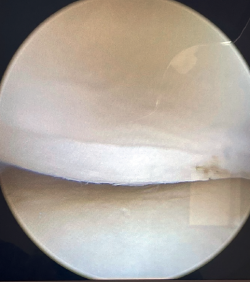

El portal de visión para la plicatura de complejo lateral será el posterolateral. Desde este portal entraremos en la corredera lateral del codo para visualizar la parte posterior de la articulación radiocapitelar. Nos permitirá visualizar también el componente lesional del Osborne-Cotterill y determinar el grado de inestabilidad posterolateral aplicando varo y supinación al antebrazo. Con este gesto podremos observar cómo la cabeza radial se subluxa a posterior y la línea articular se abre (Figura 2).

Figura 2. Apertura del espacio radiocapitelar demostrando un aumento de la laxitud patológico en el codo.